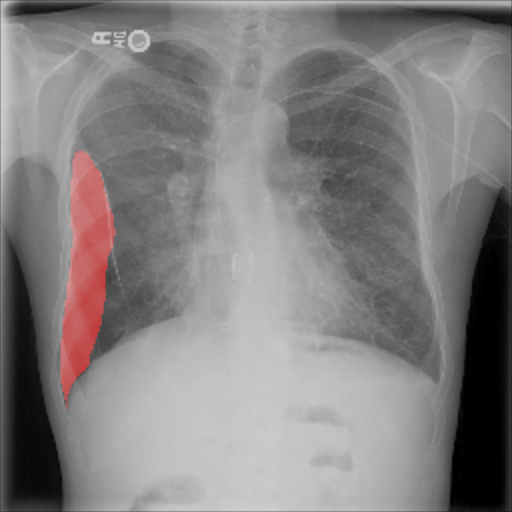

The pre-trained ResNet-50 was also employed as the patch-level classifier within the MIL approach. We chose the binary cross-entropy between the maximum patch score and the image-level label as the loss function. The batch size was selected as the number of patches per image. We trained with an initial LR of for 30 epochs and achieved an average AUC of 0.930.01 using this method. High patch scores (indicated by thicker red frames, cf. Fig. 5(c)) give a hint on the location of the pneumothorax.

As pixel-level ground truth annotations were available only for a subset of the images, 871 images in total were used for training the FCN for 400 epochs. As a loss function, a weighted cross entropy (25.0 for pneumothorax pixels and 0.5 for non-pneumothorax pixels in order to account for the smaller size of pneumothorax regions) was employed at pixel-level with an initial LR of . With an average AUC of 0.920.02, the overall performance of this method is worse than the CNN and MIL. On the other hand, the FCN generates pixel-level probabilities (cf. Fig. 5(d)), which indicate the location of the pneumothorax. The average Dice coefficient for positively classified cases is .